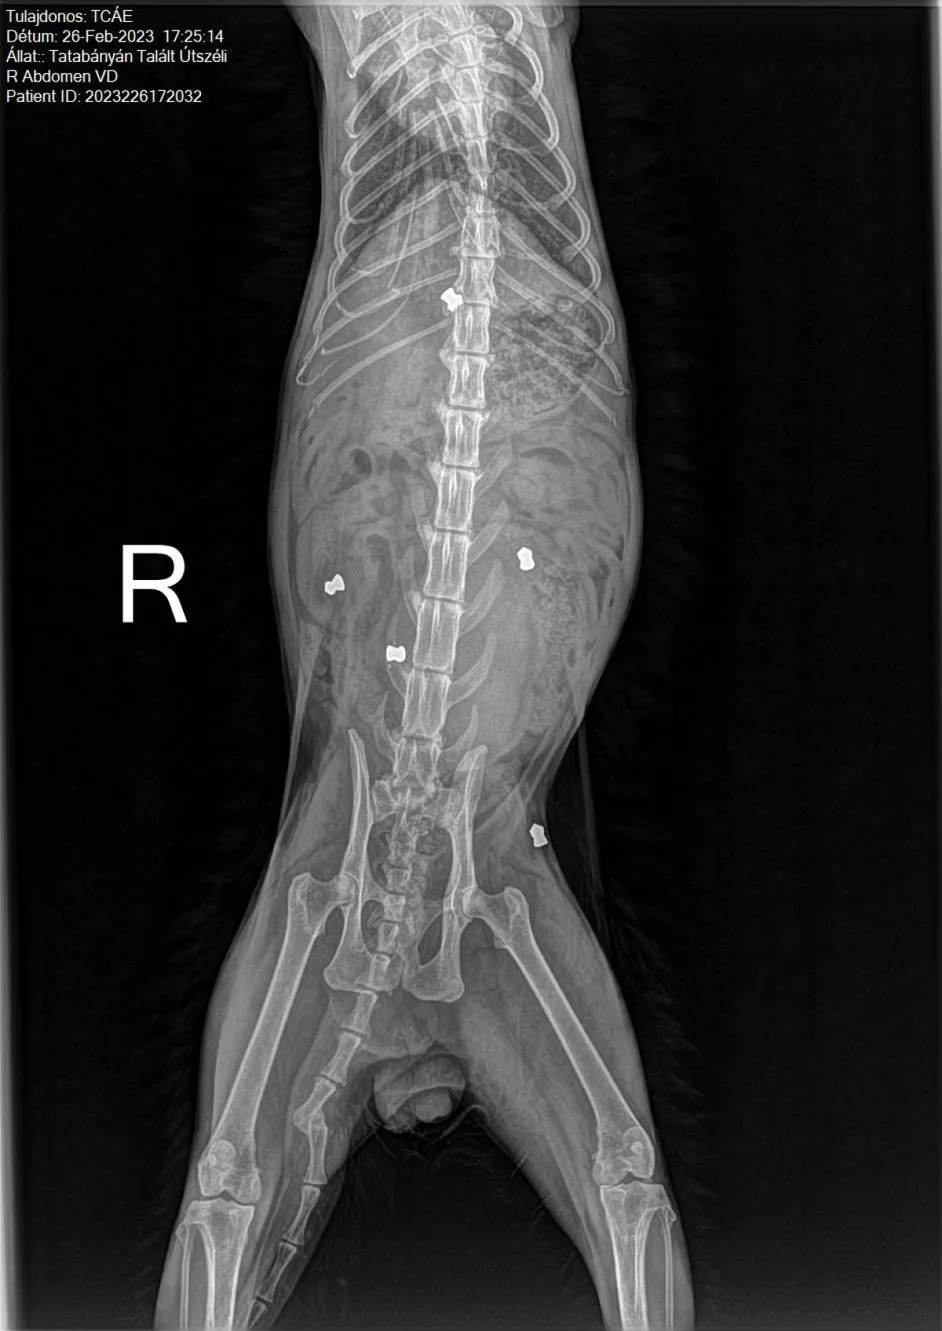

"Nyolc lövedéket mutatott a röntgen. Egyet közvetlenül a gerincében találtak meg. Azonnal küldtük a felvételeket a győri kórházba, ahol már másnap műteni akarták, de arra már nem került sor, mert súlyosbodott az állapota. Tatán kellett megműteni."